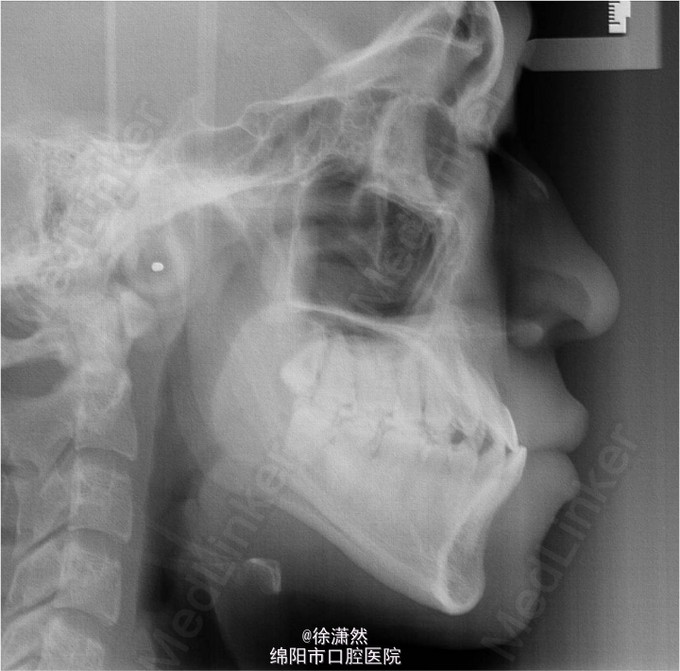

主诉:要求矫治“地包天、牙列缝隙” 男,20岁,生长停滞期,无家族遗传史,无全身系统性疾病,替牙后逐渐出现反合、牙列散在间隙

磨牙、尖牙近中关系,全牙弓反合,牙列散在间隙 下颌不能后退至切合,TMJ无弹响、压痛、杂音,无偏侧咀嚼等口腔不良习惯

诊断:Angle III类,骨性III类,垂直生长型,牙列散在间隙,反合 处理:采用正畸掩饰治疗,拔除4个第三磨牙,直丝弓矫治技术

全牙弓不调要注意后牙段横向的不调,此病例缩窄下牙弓,协调牙弓宽度,消除后牙干扰;III类牵引纠正磨牙关系、建立前牙覆合覆盖;同时肌功能训练建立舌肌与咀嚼肌的肌力平衡。多个因素共同考虑使得全牙弓反合得到矫治。